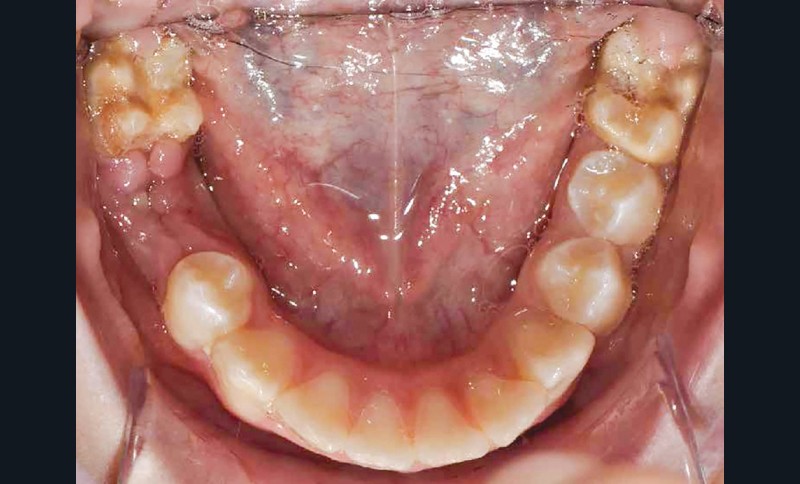

Lisa est une jeune patiente de 10 ans, atteinte d’une MIH sévère sur les premières molaires mandibulaires 36 et 46 (fig. 1 et 2). Elle présente une sensibilité exacerbée au froid en regard des zones molaires entraînant un brossage approximatif.

Afin d’optimiser les séances de soins, l’anesthésie intra-osseuse par injection électronique a été réalisée avec le Quicksleeper 5® dans les deux secteurs (fig. 3 et 4) afin de permettre la réalisation des coiffes préformées métalliques sur 36 et 46 dans la même séance (fig. 5 à 7). Il aurait été difficilement envisageable de réaliser les coiffes dans la même séance en utilisant une anesthésie tronculaire dans chaque secteur.